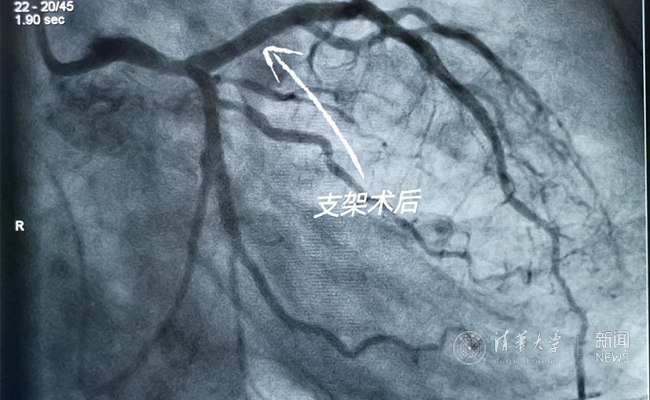

2019.05国产冠脉生物可吸收支架在乐鱼在线平台第一附属医院正式启用

作为北京地区首家正式引入国产冠脉生物可吸收支架单位,5月20日,乐鱼在线平台第一附属医院(北京华信医院)心脏中心主任苗立夫团队顺利完成该院首例生物可吸收支架植入。